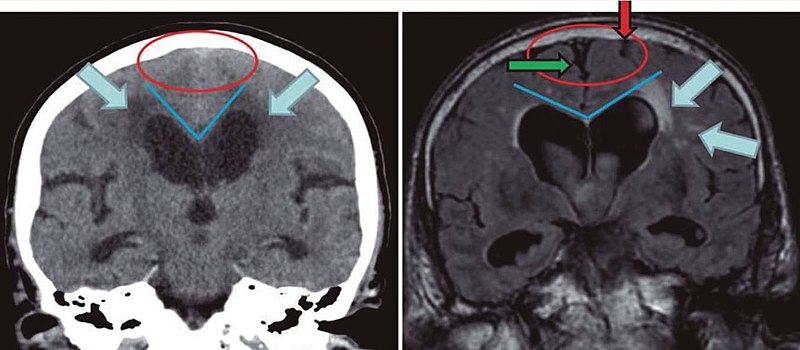

Uno de los casos más comunes de atrofia cerebral es la que se caracteriza por acercamiento entre las superficies corticales y epindimarias, ensanchamiento de los surcos cerebrales, y adelgazamiento de las circunvoluciones de los lóbulos frontales.

Los síntomas más típicos del Alzheimer son la pérdida de la memoria, ya que la atrofia cerebral la produce inicialmente en el hipocampo (estructura que se encarga de desarrollar los procesos mnésicos).

No obstante, con la progresión de la enfermedad la atrofia se prolonga hacía las otras regiones cerebrales, produciendo muchos más déficits cognitivos.

Presenta una progresión muy lenta (entre 15 y 20 años). En las fases iniciales, la patología afecta a las zonas antero-medias del núcleo caudado y dorsales del núcleo putamen, provocando alteraciones en la articulación y en el lenguaje espontáneo.

Posteriormente, en estadios intermedios, la persona suele experimentar una notable reducción de su capacidad lingüística. En la enfermedad evolucionada, la corea de Huntington suele provocar afasia de Wernicke, una marcada reducción de la fluidez verbal, escritura disgráfica y alteraciones en el procesamiento visuespacial.